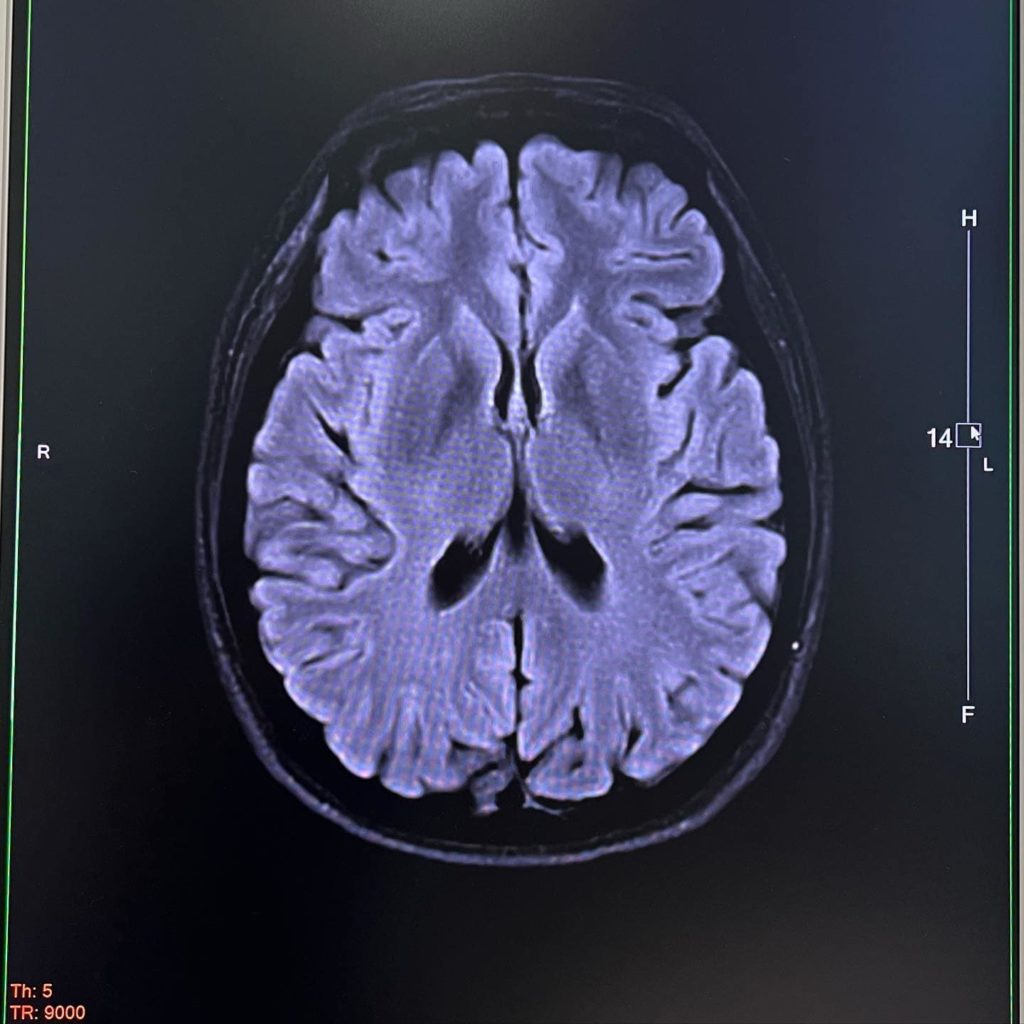

ระหว่างนั้น จ๋ามีนัดตรวจร่างกายประจำปีอยู่แล้ว มีตรวจแพคเกจใหญ่ มีส่องกล้องลำไส้ เลยจอส่องกล้องกระเพาะอาหารด้วย และตรวจเลือด ตรวจมะเร็ง รวมถึงตรวจ MRI สมองไปด้วย เพราะพอช่วงเครียดๆ ร่างกายมันรู้สึกรวนไปหมด อยากตรวจแบบ set zero ไปเลย ถ้าไม่เป็นอะไรก็เคลียร์ ว่าตรวจปี 2022 ผลปกติดีทุกอย่าง